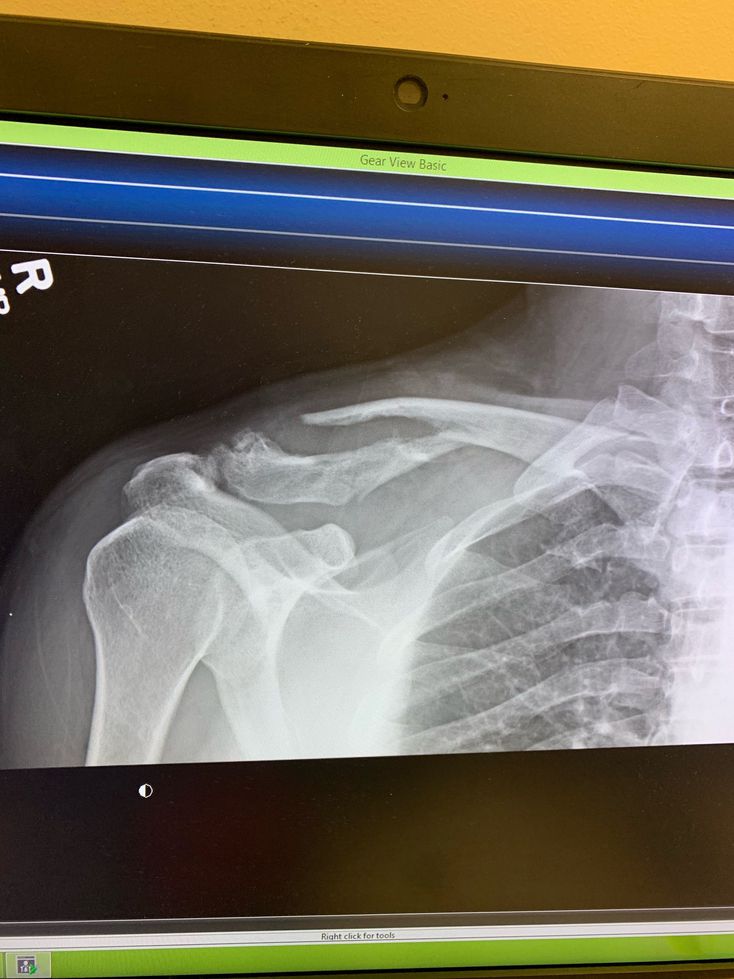

X-ray

Xray

Broke

Gottahurt

Clavicle fracture